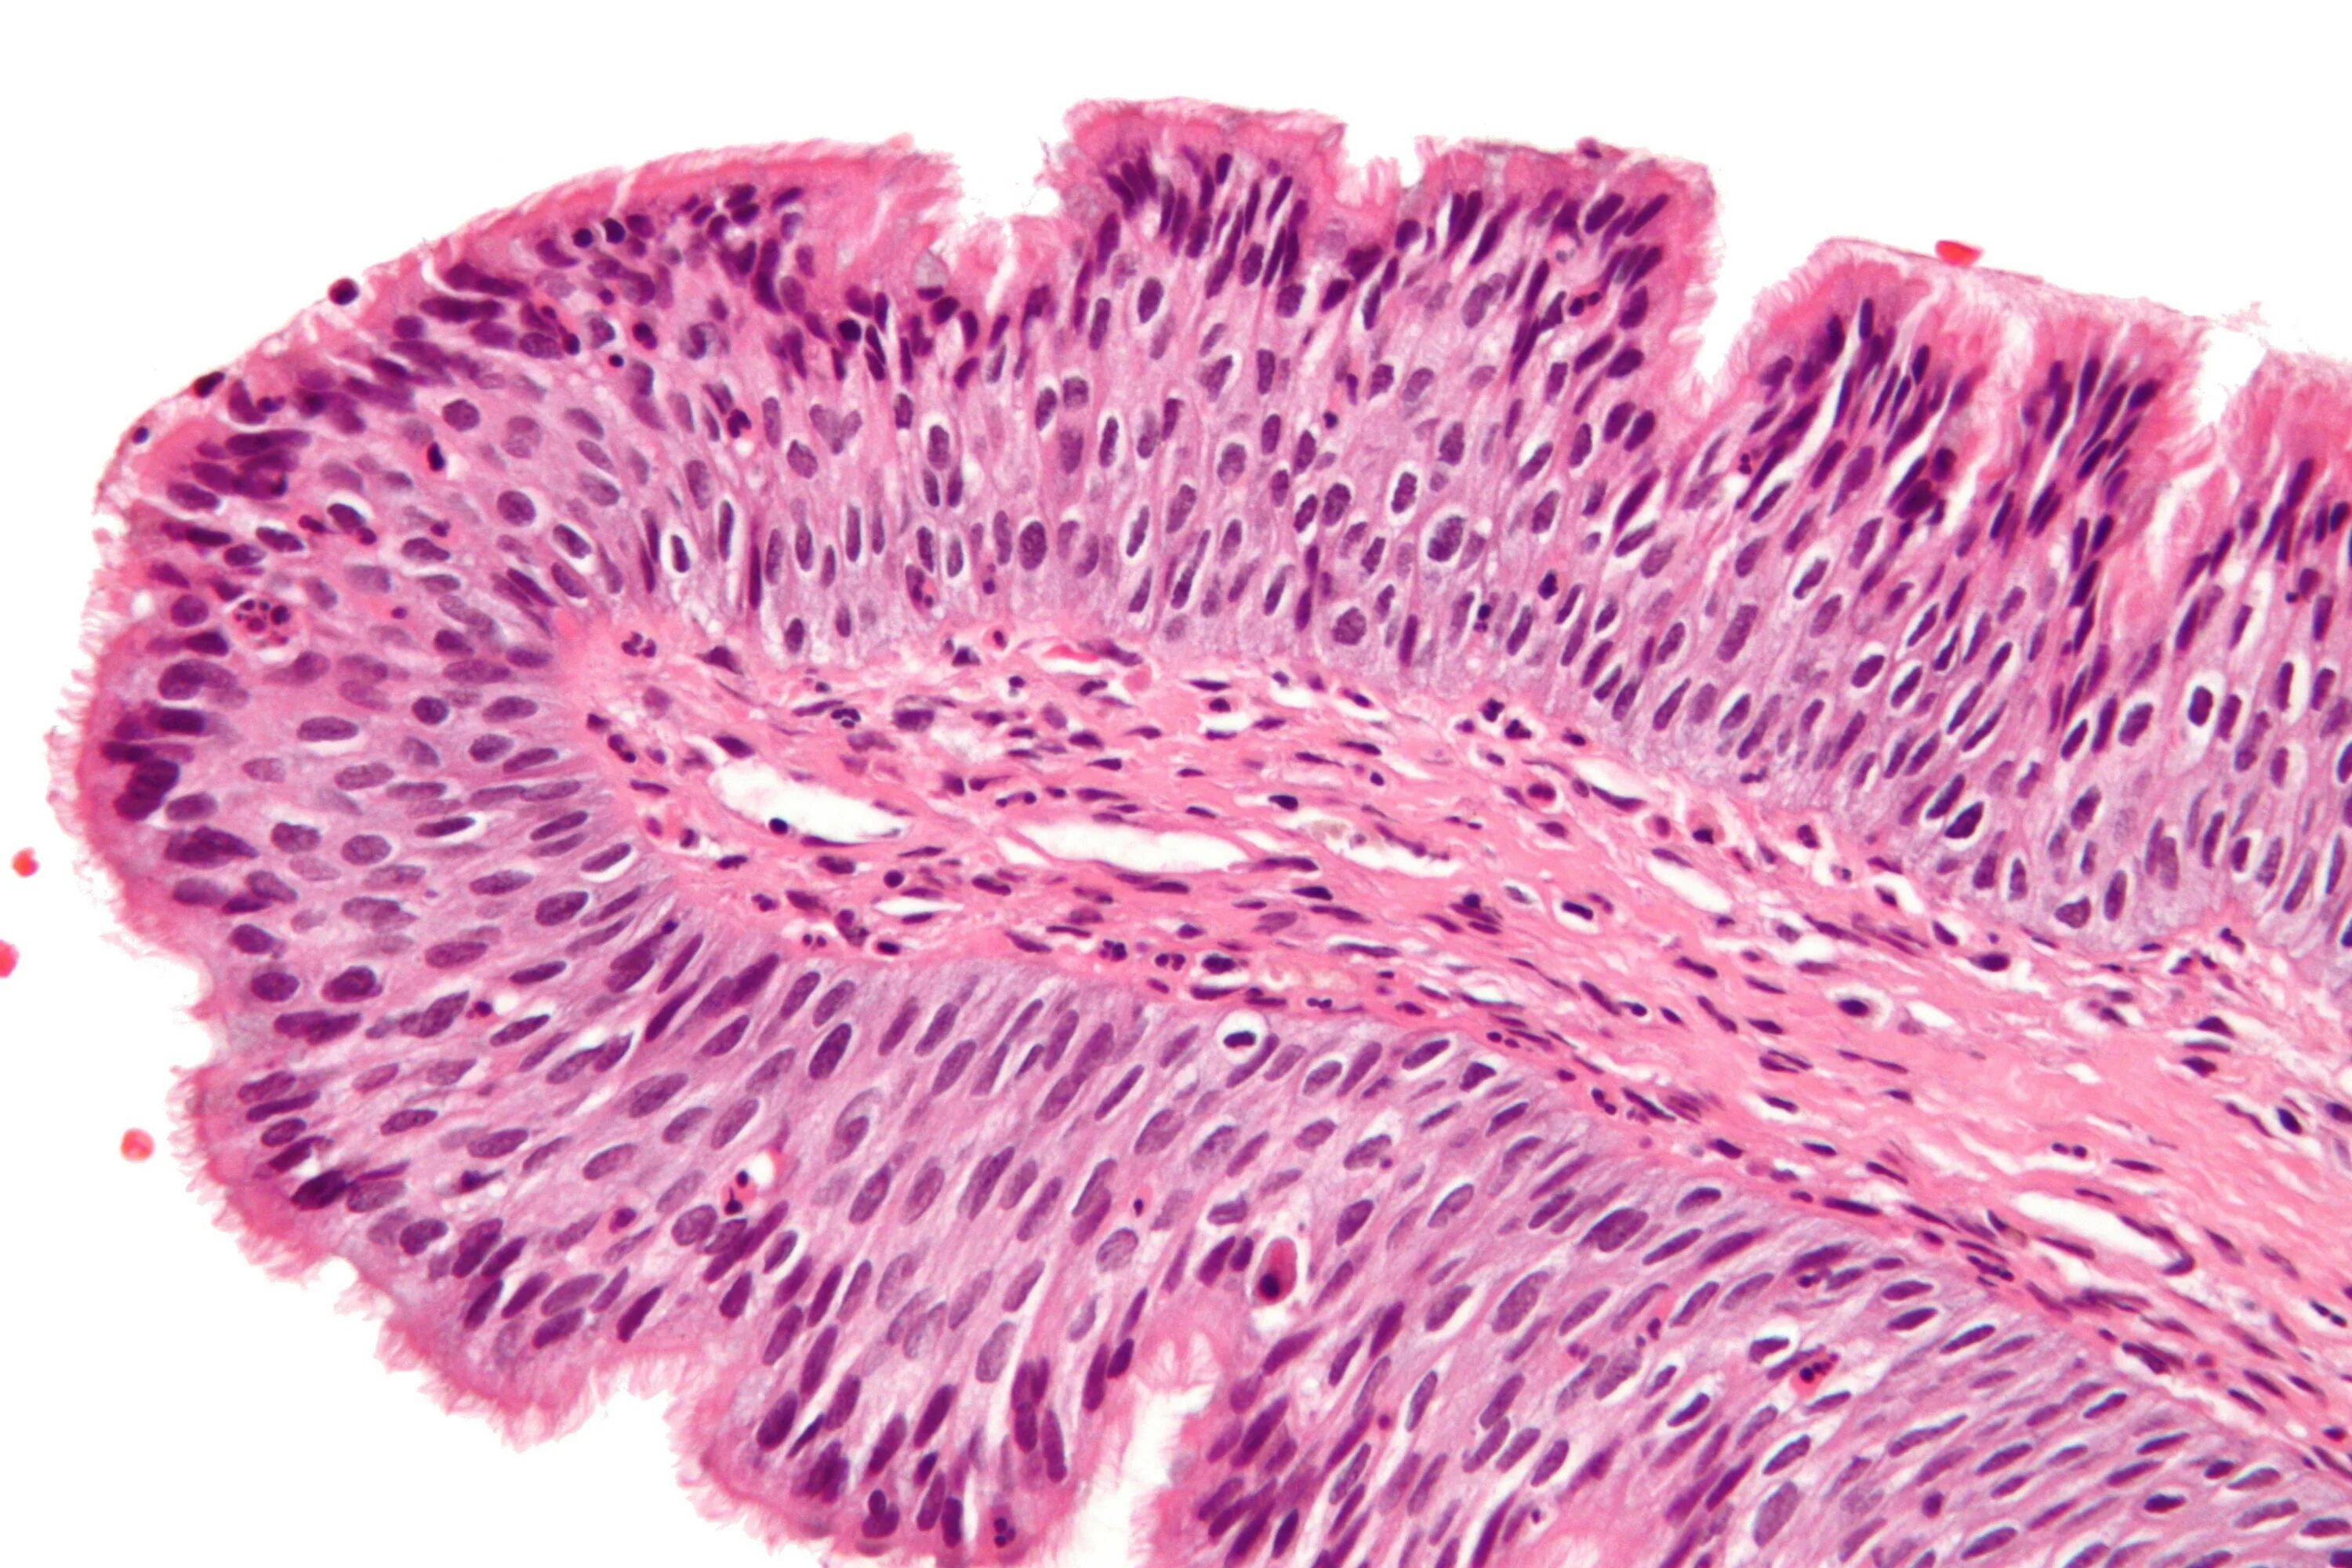

Папиллома гистология